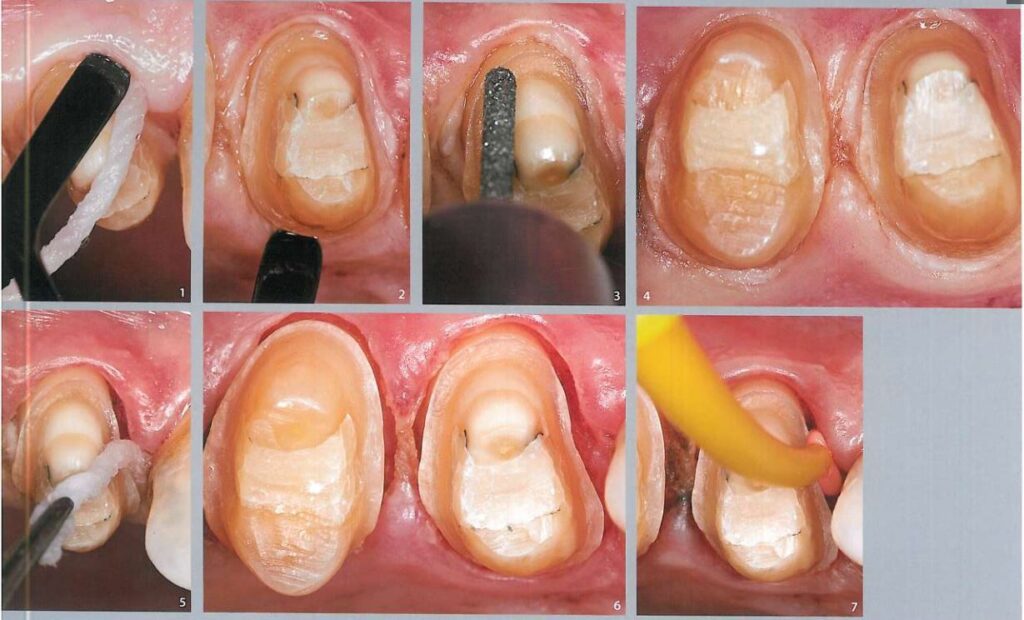

Lấy dấu yêu cầu phải ghi lại chính xác kích thước cùi răng, vị trí mô mềm, đặc biệt là hình dạng đường hoàn tất và mối tương quan giữa cùi răng với các răng kế cận trên cung hàm (H1).

Khi sử dụng kĩ thuật đặt chỉ đôi (2 sợi), thì sợi chỉ với đường kính nhỏ hơn được đặt vào trước tiên. Sợi chỉ đầu tiên này nhằm giúp ngăn ngừa máu và dịch trào lên khi rút sợi chỉ thứ 2 ra (H3,4).

Hình 5 minh họa sợi chỉ thứ nhất được đặt vào khe nướu, tách nướu rời xuống khoảng 0.5 – 1 mm nhằm ngăn sự tiếp xúc của đầu mũi khoan với biểu mô nướu trong quá trình điều chỉnh đường hoàn tất.

Sau đó dùng mũi khoan mài điều chỉnh tiếp đường hoàn tất nếu cần (H6).

Sợi chỉ thứ 2, với kích thước lớn hơn (chỉ Ultrapak #2, Ultradent) đặt vào khe nướu để tách mô nướu sang bên, chỉ này không nhất thiết phải nằm hoàn toàn trong khe nướu mà có thể chỉ nằm trên bề mặt (H7, 8).

Hình 9 mô tả vị trí lí tưởng của 2 sợi chỉ trong khe nướu, khi đó khe nướu rộng sang bên > 0.5 mm và tách xuống dưới > 0.5 mm để cho phép ghi dấu 1 phần mô răng lành bên dưới đường hoàn tất.

Khi chuẩn bị lấy dấu, phải thổi khô dịch và nước bọt xung quanh, sau đó gắp sợi chỉ ở trên ra (H10).

Ngay lập tức bơm cao su lỏng vào khe nướu (H11).

Bơm hết lượng cao su còn lại lên cùi răng và lấy dấu. Dấu lấy ra phải thấy rõ đường hoàn tất.

Gắp sợi chỉ còn lại ở trong ra.